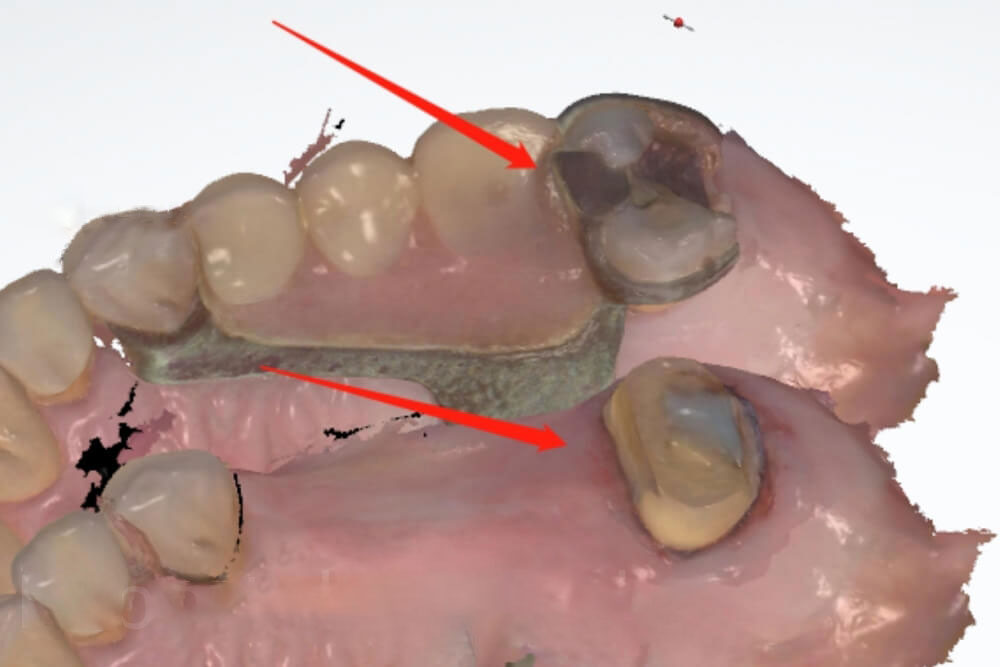

1. Wrong way for Fit to partial

Let’s see a real case example. Our dental clinic sent 2 scans to us. One scan was with the partial in the patient’s mouth, while another scan was with a prepared tooth. The dentist asked us to 100% copy the patient’s original molar tooth, so the crown could fit to the her existing partial. Unfortunately, we could not help the dentist fit to partial, because the partial covered the natural tooth in the scan. In this case, we could only make a crown with our experience, so the dentist would have to make adjustments.